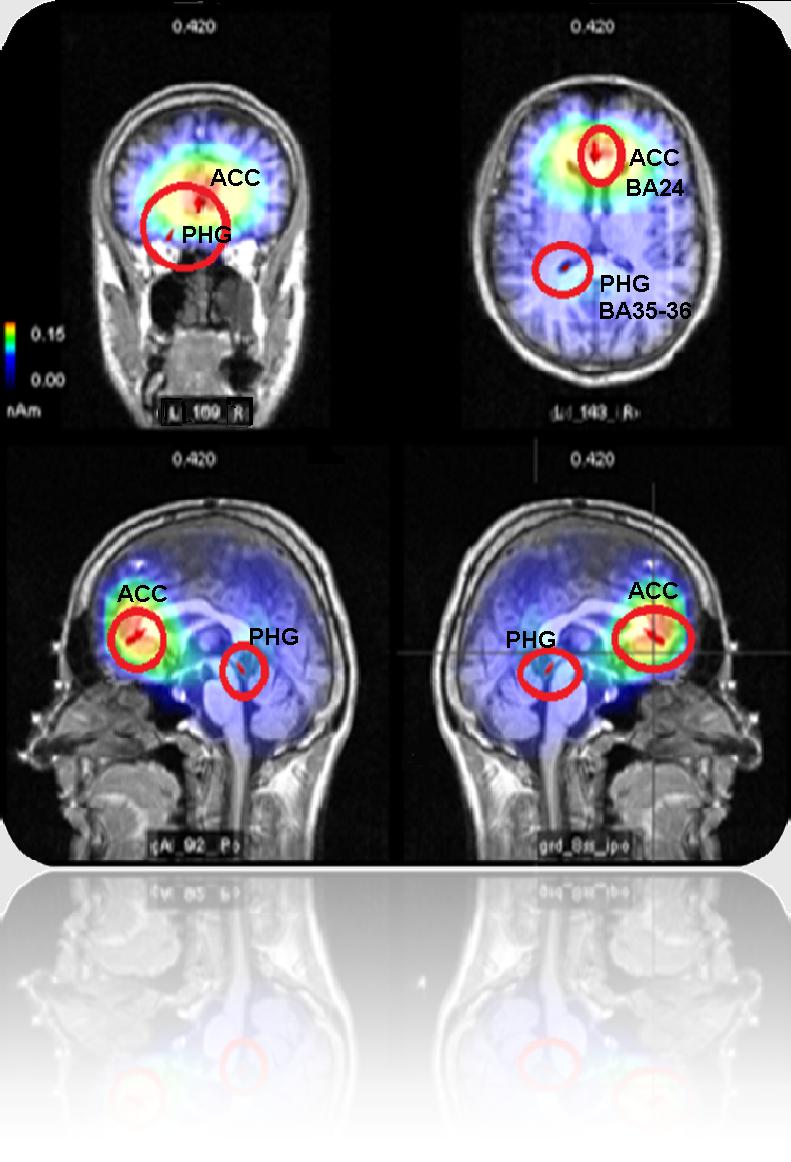

“Grazie alla tecnica di risonanza magnetica tridimensionale Loreta (Low resolution electromagnetic tomography) è stato possibile inoltre evidenziare un’attivazione della corteccia cingolata anteriore mediale e del giro para-ippocampale dell’emisfero sinistro che suggeriscono uno stato di sforzo o sofferenza indotta dall’ipossia”, conclude Zani. “I dati emersi hanno importanti implicazioni per gli individui che operano in ambienti estremi, per lo studio dei processi nervosi implicati negli stati di coscienza e nei pazienti in stato di sofferenza cerebrale. Rilevanti risultano inoltre gli effetti dello stress da esposizione prolungata ad ambiente pressurizzato, qual è quello degli aerei (ipossiemia da volo) o all’aria condizionata al livello del mare (ipossia normobarica), dove manca il ricambio di aria naturale”.